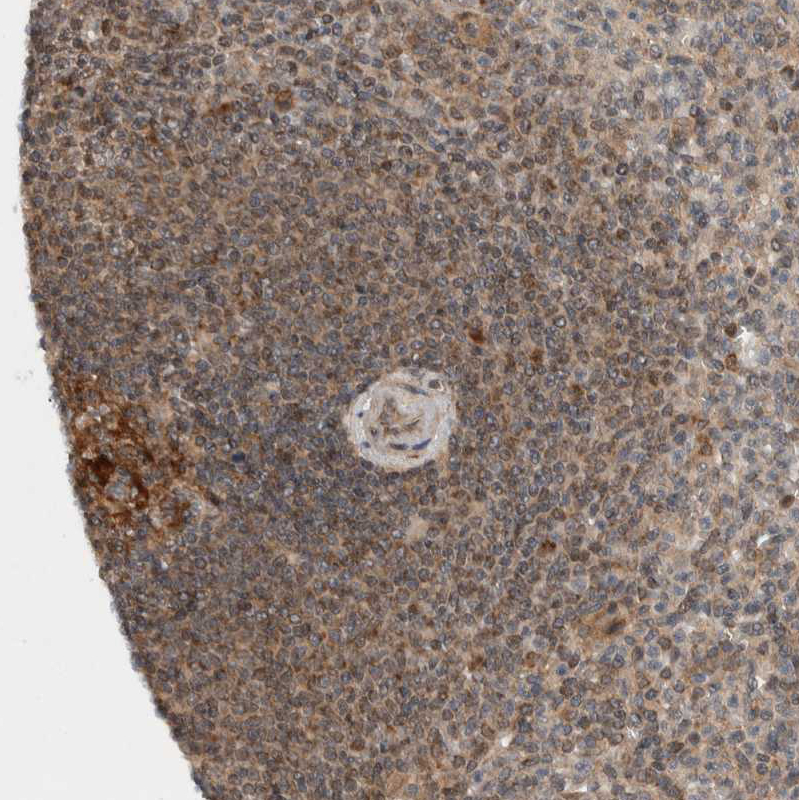

Immunohistochemical staining of human Lymph node shows moderate cytoplasmic positivity in germinal center cells.